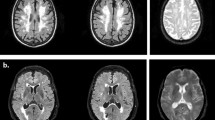

Table 3 shows findings from the assessment of cerebrovascular burden, hippocampal atrophy (HA) and insular atrophy (IA) on neuroimaging. Computed tomography (CT) scans were available for 34 controls (44% of the CN sample) and for all MCI participants except 3 naMCI subjects who refused the exam. Magnetic Resonance Imaging (MRI) scans were available for 14 controls (18% of the CN sample) and for just less than two thirds of the overall MCI subjects (66% aMCI, 60% naMCI). As anticipated, HA was greater in the aMCI group and deep WML (DWML) were more severe in the naMCI group. MRI-based ratings of cerebrovascular burden and HA were consistent with the CT findings (Supplementary Table S1).

CT imaging was performed on a 64-slice CT scanner (OptimaCT660, GE Healthcare, Milwaukee, WI; tube voltage 120 KVp, tube current 150–350 mA with automatic modulation, slice thickness 0.625 mm, field of view (FOV) 250 × 250 mm2, matrix size 512 × 512). MRI was performed on a 3-T scanner (Achieva, Philips Medical Systems, Eindhoven, the Netherlands) using a standard acquisition protocol including the following sequences: (a) T1-weighted (relaxation time (TR) 9.9 ms, echo time (TE) 4.6 ms, flip angle (FA) 8°, slice thickness 1 mm , slice gap 0, FOV 240 × 240 mm2, matrix size 240 × 240), (b) T2-weighted turbo spin echo (TSE) (TR 2,491 ms, TE 77 ms, FA 90°, slice thickness 4 mm, slice gap 0, FOV 230 × 230 mm2 , matrix size 505 × 512), (c) Fluid-attenuated inversion recovery (FLAIR) (TR 11,000 ms, TE 125 ms, FA 90°, slice thickness 4 mm, slice gap 0, FOV 230 × 230 mm2, matrix size 249 × 344).

Cerebrovascular burden and atrophy of the insula and hippocampus were assessed on CT and MRI brain scans by means of standard semi-quantitative visual rating scales. DWML and periventricular white matter lesions (PVWML) were evaluated by means of a slightly modified version of Fazekas' scale74, scored on axial CT scans and on axial FLAIR MRI scans. Due to the acknowledged vascular (i.e. ischaemic) aetiology of DWML (see Supplementary Methods) the DWML score was used in the correlation analyses. HA was rated by means of Kim's 5-point scale126 on axial CT and axial T1-weighted MRI scans and by means of Scheltens' 5-point scale127 on coronal T1-weighted MRI scans. HA was rated separately for the right and left hemispheres and the average HA score was used in the correlation analyses since this measure has been shown to be particularly sensitive to AD128. IA was assessed on coronal T1-weighted MRI scans by means of the 4-point frontoinsula (FI) rating scale76, which was rated separately for the right and left hemispheres and then combined in an overall average score for use in the correlation analyses. All these scales are described in detail in the Supplementary Methods.